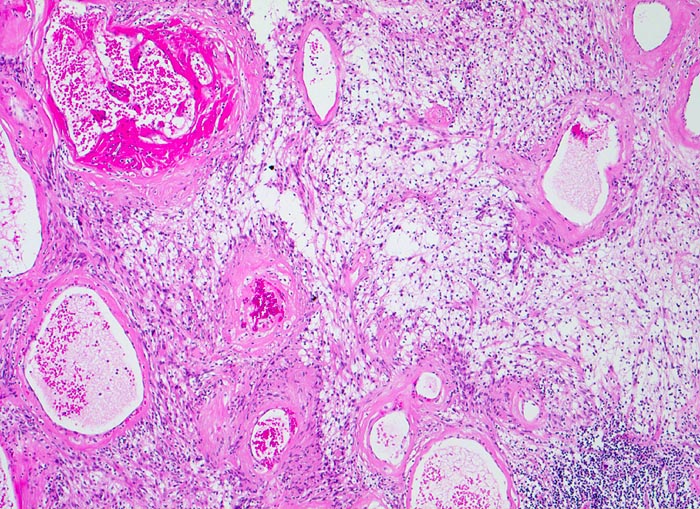

PathoPic – image database / PathoPic ID 4299 - Schwannom mit degenerativen Veränderungen

Schwannom mit degenerativen Veränderungen

Tumor mit hyalinisierten ektatischen Gefässen mit älteren Thrombosen. Biphasischer Tumor mit kompakten spindelzelligen parallel ausgerichteten Tumorzellverbänden (Antoni A Muster, rund um die Gefässe) und lockeren Verbänden von Zellen mit runden Kernen und spinnwebenartigen Zellfortsätzen (Antoni B Muster). Fokales lymphozytäres Entzündungsinfiltrat.

Tumor im Musculus soleus, 2cm Durchmesser